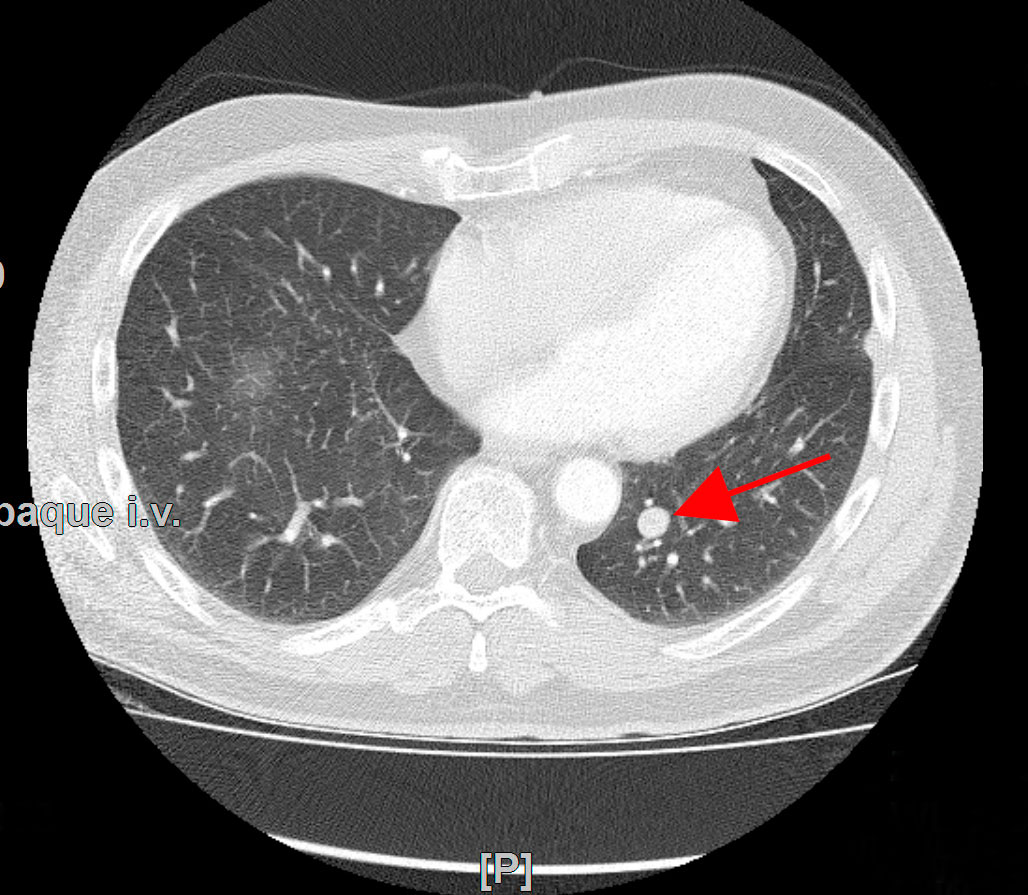

Lungenkrebs

Lungenkrebs befällt etwa 25 Prozent aller Krebskranken und gilt als häufigster Tumor beim Mann. Doch auch immer mehr Frauen sind betroffen. Die chirurgische Therapie ist für uns Mittel der Wahl, sofern keine Fernmetastasen vorhanden sind. Dabei können wir in unserer Klinik technisch hoch anspruchsvolle Lungenoperationen auf endoskopische Weise videoassistiert vorgenommen werden.

Lungenmetastasen

Werden neben Lungenkrebs auch Lungenmetastasen diagnostiziert, stellt das die Medizin vor höchste Herausforderungen. Nur wenige Kliniken sind darauf spezialisiert, bei dieser Erkrankung chirurgisch einzugreifen. Durch besondere fachliche Expertise, einen großen Erfahrungsschatz und die technische Ausstattung ist unsere Klinik Ihr Ansprechpartner, wenn es um die chirurgische Therapie von Lungenmetastasen geht.

Laser-Chirurgie bei Lungenmetastasen

In unserer Klinik für Thoraxchirurgie werden zahlreiche Operationen an der Lunge mit dem modernen 1318NM-Diodenlaser durchgeführt. Das neue Gerät wurde speziell für die Lungenchirurgie entwickelt und hat besondere Eigenschaften, die das Schneiden von Lungengewebe ermöglichen: Mit dem Laser ist der Thoraxchirurg in der Lage, bluttrocken und übersichtlich durch das Lungengewebe zu schneiden. Dadurch können Metastasen und Tumoren, die tief im Lungengewebe liegen, onkologisch sicher entfernt werden. Anhand dieses modernen Verfahrens kann der Thoraxchirurg besonders gewebeschonend vorgehen und zahlreiche Lungenmetastasen entfernen, was mit konventionellen Methoden nicht möglich wäre. So kann die Prognose für den Patienten verbessert werden. Die sogenannte Laser-Metastasektomie ist eine etablierte chirurgische Behandlung, die bundesweit nur in großen Thoraxkliniken vorgenommen wird. Unsere Klinik ist die einzige in Ostwestfalen-Lippe, die Laser-Chirurgie bei Operationen der Lunge anbietet.

- Lungenrundherd (Lungenverschattung)

Gutartige Lungentumoren

Gutartige Lungentumoren sind Bronchialadenome (gutartiger Drüsentumor), Chondrome (Knorpelgeschwulst), darunter am häufigsten die sogenannten Hamartome, Osteome (Knochengeschwulst), Fibrome (Bindegewebsgeschwulst), Lipome (Fettgewebsgeschwulst), Tuberkulome (oft verkalktes Narbengewebe nach abgeheilter Lungentuberkulose). Bis auf Tuberkulome kommen die genannten gutartigen Lungentumoren selten vor. Bei sämtlichen Fragestellungen zu gutartigen Lungentumoren sind wir Ihr vertrauensvoller und kompetenter Ansprechpartner.

Tumornachsorge

Bei der Tumornachsorge geht es darum, nach Therapie eines Krebsleidens eine regelmäßige ärztliche Kontrolle konsequent und dauerhaft durchzuführen. Damit soll bei Patienten mit Lungenkrebs ein erneutes Auftreten des Tumors in der Lunge oder in anderen Organen (Fernmetastasen) frühzeitig zu erkennen. Durch ein frühzeitiges Feststellen eines erneuten Auftretens eines Tumors wird eine frühzeitige Behandlung möglich noch bevor Beschwerden auftreten. In der Nachsorge werden nicht nur körperlichen Symptome, radiologische und Laborkontrollen erfasst, sondern auch psychosoziale Probleme sowie Fragen zur Berufs- und Arbeitsfähigkeit mit dem Patienten diskutiert und Lösungsvorschläge angeboten. Dies geschieht in engem Bezug zum Hausarzt und Lungenfacharzt.

Die Nachsorge soll in enger Kooperation mit dem Hausarzt oder Lungenfacharzt durchgeführt werden. Prinzipiell sind alle Patienten mit einem Lungenkrebs für fünf Jahre der Nachsorge zuzuführen. Dabei schließt sich diese an die Behandlung durch Operation, Strahlen- oder Chemotherapie nahtlos an und sollte bereits nach der ersten Behandlung in der Klinik organisiert werden.